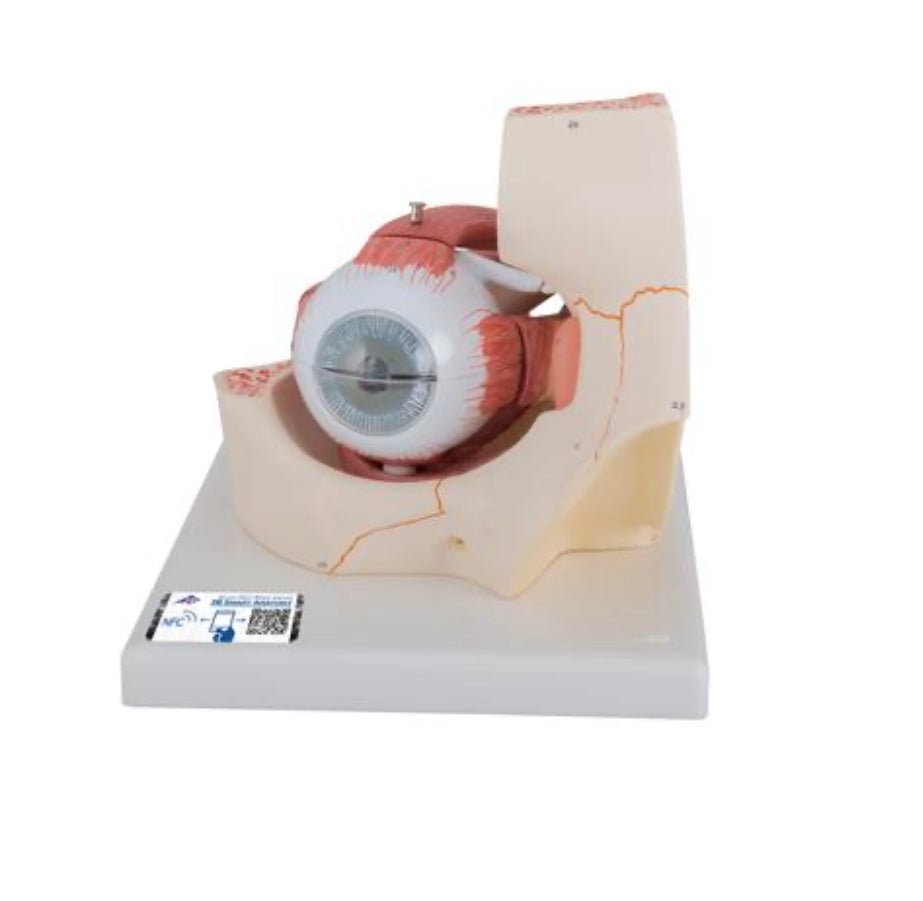

Selling anatomical models is the mainstay of eAnatomi, although we also spend a lot of resources developing our own anatomical materials such as posters. Anatomical models are used for various purposes and can show both defined tissues, organs and organ systems. Are you looking for a simple model of bone tissue or perhaps an advanced torso model based on MRI technology, you can find it all at eanatomi.com.